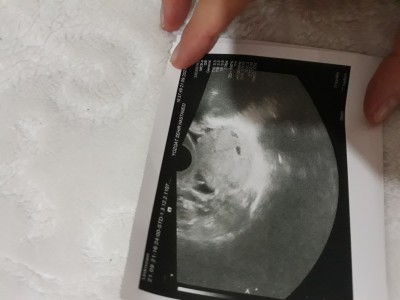

Kızlar ilk gittiğim doktor ikiz bebek dedi doktor değiştirdim bu da ikiz göremiyorum dedi sizce bebek bebeğin arkasına falan geçermi böyle bi durumla karşılaşan varmi

Gebelik haftası 10+3

(545 puan)

İkiz diyen doktor alttan baktı 2. Gittiğim doktor sadece karnımdan baktı bebeği zor gördü hafta olarak küçükte olabilir dedi bakalım bu gittiğimde ne diyecek